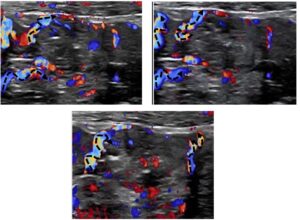

The thickened wall was significantly hyperperfused. Winding mesenteric veins could be seen running towards the thickened bowel loop.

Winding mesentric veins (dashed arrows) running towards a thickend painful jejunal loop

In contrast to inflammatory hyperperfusion, where only tiny veins inside the bowel wall are distended, here, larger veins in the mesentery also showed distension and winding, indicating gravitational congestion, comparable to varicose veins in the legs in some patients .

An obvious differential diagnosis of a hyperperfused and thickened jejunal wall would be a chronic inflammatory bowel disease. However, while inflammation is characterised by numerical increase of multiple small vessels restricted to the mucosa or submucosa of the small bowel, this patient exhibited in addition large winding vessels within the mesentery , indicating distension of the veins inside the mesentery and bowel wall due to orthostatic distension caused by congestion.